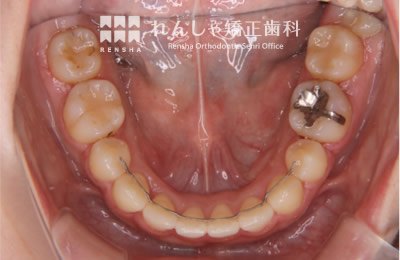

中高生

永久歯列はほぼ完成してしますが、歯列を側方だけでなく後方へも拡大し、埋まっていた右上奥歯を引っ張り出しています。

| 主訴 | 埋まったままでてこない歯がある |

|---|---|

| 診断名 | Angle Class II 小臼歯の埋伏と叢生を伴う上顎前突 |

| 初診時年齢 | 13歳5か月 |

| 装置名 | マルチブラケット装置 |

| 抜歯非抜歯 | 非抜歯 |

| 治療期間 | 2年3か月 |

| 費用の目安 | 約82万円+消費税(検査料金、都度の処置費用等も合わせた総額) |

| リスク副作用 | 歯の移動に伴う軽微な歯根吸収、歯槽骨吸収、歯肉退縮(本症例では軽度の歯根吸収を認めた)、矯正器具装着中のカリエスリスク増大(本症例ではカリエス発生無し) |